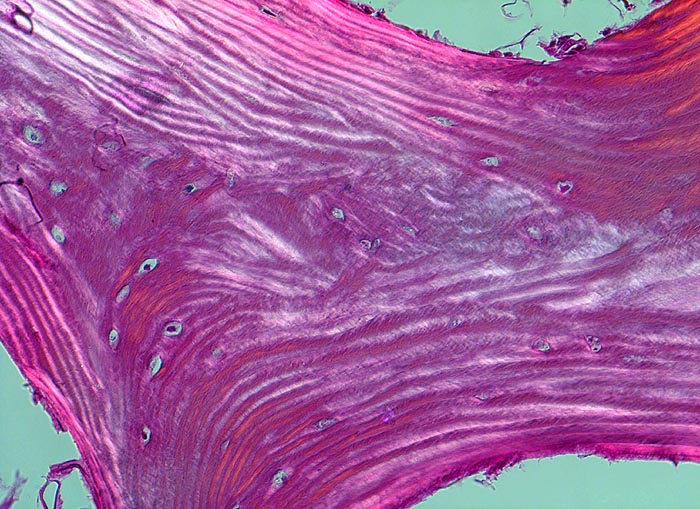

Morphologische Merkmale:

• Tibiametaphyse mit angrenzendem Weichteilgewebe.

• Das Sarkom infiltriert diffus den spongiösen Knochen der Diaphyse und hat präexistente Knochenbälkchen verdrängt.

• Der Tumor hat die Korticalis destruiert und infiltriert die angrenzende Skelettmuskulatur.

• Der Tumor besteht aus neugebildetem bereits verkalktem Knochen oder einem Netzwerk von primitiven Osteoidtrabekeln. Entlang oder innerhalb der Osteoidtrabekel lokalisierte polymorphe Tumorzellen mit ausgeprägten Kernatypien und zahlreichen Mitosen. Leicht verwaschene Kernstrukturen als Folge der Gewebsentkalkung.